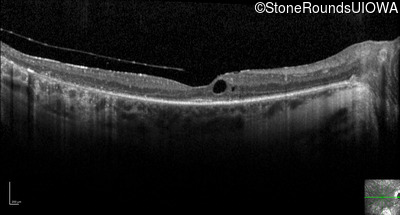

Optical Coherence Tomography - Right - 20/40 +1

Exemplar / OCT Stack